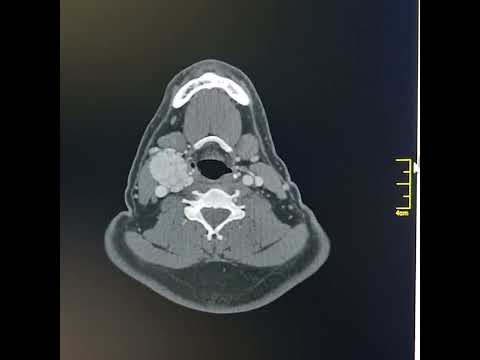

Hellow guys, Welcome to my website, and you are watching Carotid body tumour - shamblin type 2. and this vIdeo is uploaded by Shirish Patil at 2022-10-01T22:26:34-07:00. We are pramote this video only for entertainment and educational perpose only. So, I hop you like our website.